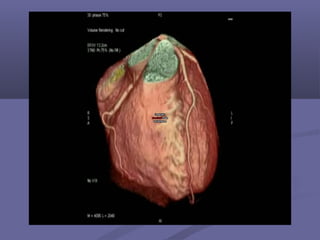

Other Indications:Other Indications:

 TumorsTumors

Other Indications:Other Indications: Post-bypassPost-bypass  Post-stentPost-stent  TumorsTumors